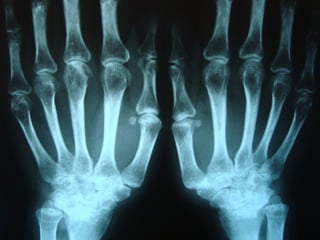

Achados radiográficosAchados radiográficos

 Osteopenia peri-articularOsteopenia peri-articular

 Diminuição do espaço articularDiminuição do espaço articular

 Presença de cisto e erosõesPresença de cisto e erosões

 Edema de partes molesEdema de partes moles

 Presença de deformidadesPresença de deformidades